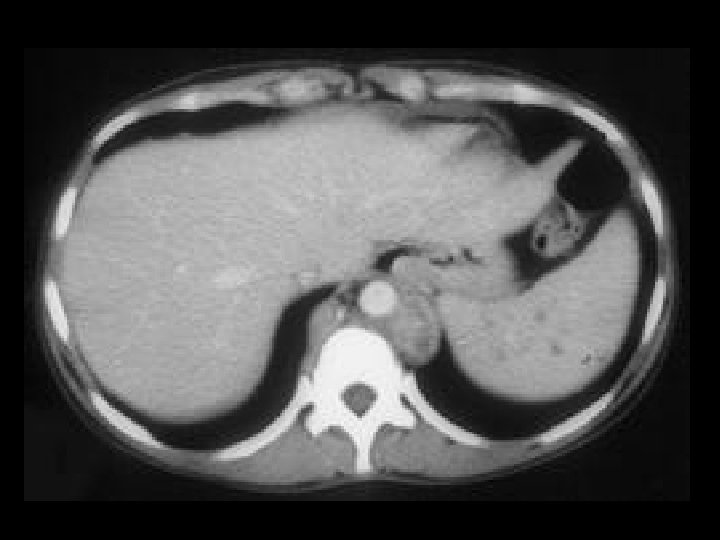

Lymphoma • Findings: – Innumerable low density lesions of the liver and one in the spleen • ddx: – Metastatic disease – Fungal abscesses